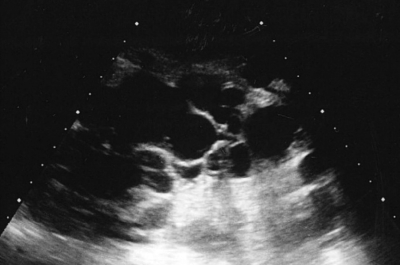

血圧 146/92 mmHg。尿所見:蛋白(+)、潜血(-)。血液生化学所見:尿素窒素 20 mg/dL、クレアチニン 1.2 mg/dL。左の側腹部の腹部超音波像と腹部 CT の冠状断像とを別に示す。